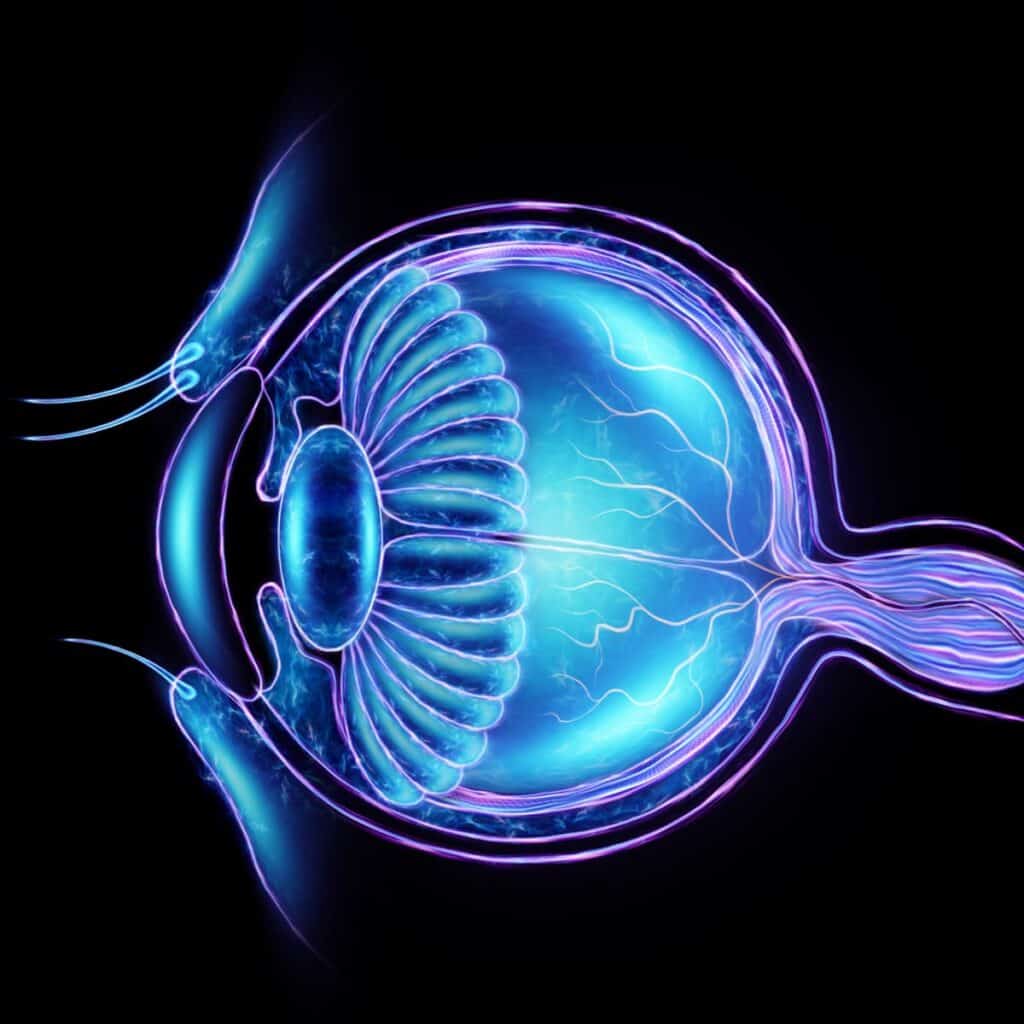

7. Supporting Eye Health

Both vitamins A and D, found in cod liver oil, are essential for maintaining optimal eye health. Vitamin A is crucial for the proper functioning of the retina and may contribute to the prevention of age-related macular degeneration (AMD), a leading cause of vision loss in older adults.

8. Prenatal Health and Development

Cod liver oil is a valuable supplement for pregnant women due to its rich content of omega-3 fatty acids, vitamin A, and vitamin D. These nutrients are essential for fetal development, including the development of the brain, eyes, and bones. Proper maternal intake of cod liver oil may also reduce the risk of preterm birth and support the overall health of both mother and baby.